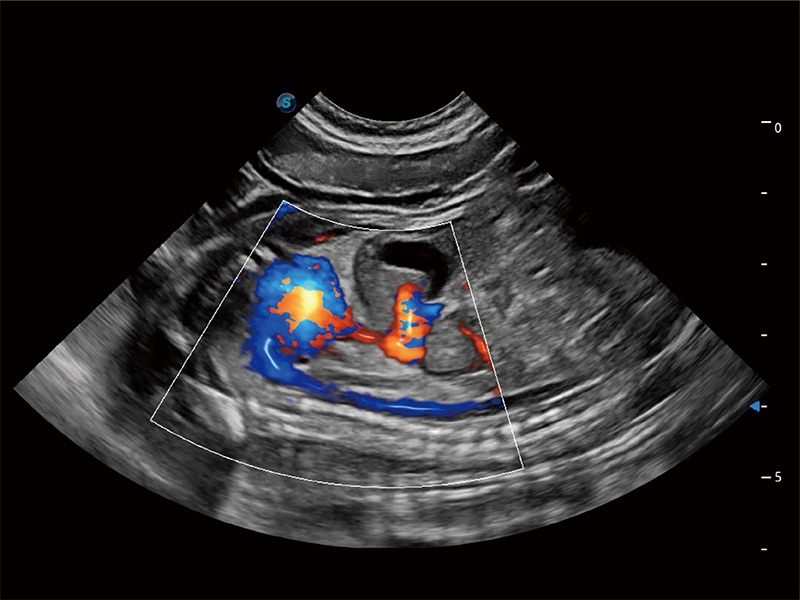

ProPet 80 配备了丰富的心脏探头群、先进的成像技术和专业的心脏测量工具,可帮助动物医生为不同体型和生理结构的动物提供心脏和心肌功能的全面评估。

能够增加心肌组织与血流之间的区别。对于心脏扫查困难的动物,可提供更好的心内膜边界的显示。

能够基于左心室壁追踪和辛普森法,自动计算射血分数,支持多个可移动点描迹,与手动测量相比,极大节省了动物医生的时间和精力。